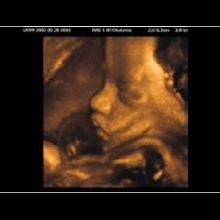

Eine ganz besondere Faszination bieten die neuen 3D/4D Ultraschallgeräte.

Die 3D-Sonografie erlaubt die einzigartige räumliche Darstellung des ungeborenen Kindes. In der 4D-Technik werden Bewegungsabläufe in nahezu fotorealistischer Weise in Echt-Zeit (Real-Time) mit bis zu 25 Bildern/sec. möglich- ein faszinierender Einblick in die Welt des Ungeborenen.

HIER EINE AUSWAHL VON 3D-ULRASCHALL-BILDERN: